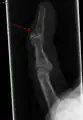

- La radiografía que muestra fractura en la inserción del tendón extensor

- Un dedo en martillo sin una fractura asociada